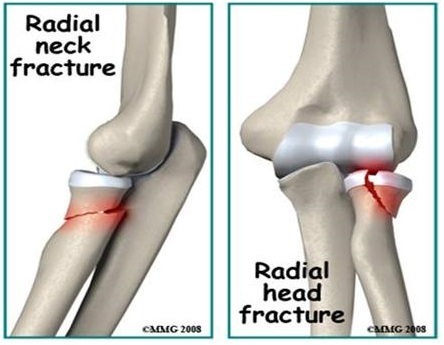

Which fracture usually occurs when there is a fall onto an outstretched arm?

Radial head and neck fractures